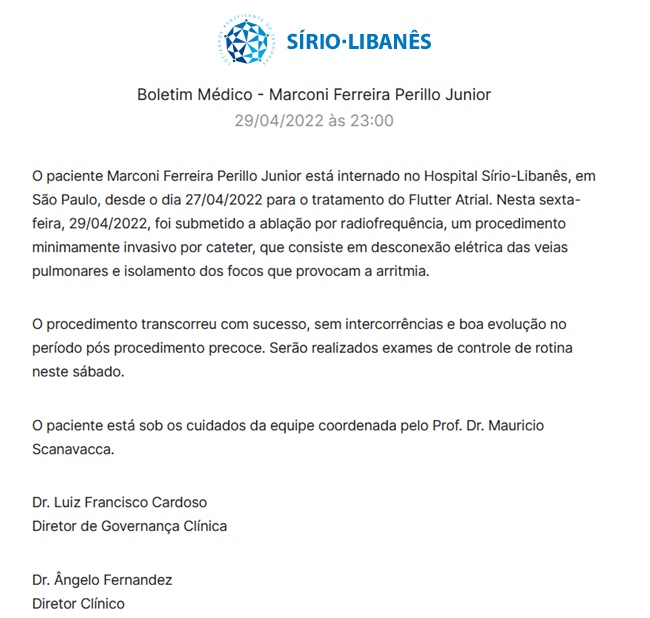

O ex-governador de Goiás Marconi Perillo (PSDB), internado desde a última quarta-feira ,27, no Hospital Sírio-Libanês, em São Paulo, foi submetido a um procedimento médico para tratar arritmia cardíaca na noite de sexta-feira 29.

De acordo com o boletim médico divulgado pelo hospital, o procedimento ocorreu com sucesso e não teve intercorrências. Veja abaixo:

O político deve passar por novos exames neste sábado, 30. Segundo o boletim, o ex-governador estava internado devido a um quadro de “flutter atrial”. Trata-se de um funcionamento irregular do ritmo cardíaco. É caracterizado por sintomas como palpitação e, às vezes, fraqueza, intolerância a esforço e dispneia.